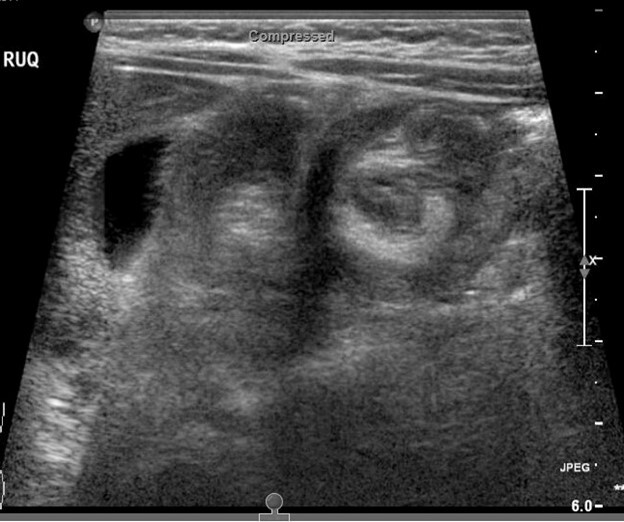

Evaluation may show a right upper quadrant mass or “sausage sign.” However, the absence of this on examination does not eliminate the need for further evaluation for intussusception, nor does the absence of pain at the time of presentation. Radiographs may show a paucity of bowel gas on the right, loss of the liver edge, and may even reveal the intussusception itself. (See Figure 3.) This is identified as a donut-like shape or “target sign” in the right upper quadrant, or as an intraluminal mass within the transverse colon, which may be identified by the “crescent sign” or “meniscus sign” of air within the lumen of the colon at the leading edge of the intussusceptum.28 The abdominal radiographs are abnormal in only 45% of cases of intussusception.30

Figure 3. Intussusception |

![]() |

The top image is a radiograph with intussusception visible along the edge of the liver. The bottom image is an ultrasound of intussusception. Images courtesy of Derya Caglar, MD. |

Ultrasound has become the primary and preferred method for diagnosing intussusception in the pediatric population. It has high sensitivity (98% to 100%) and specificity (88% to 100%) in the diagnosis of intussusception.33,34 (See Figure 3.) Air contrast enema reduction of intussusception has become standard, although it occasionally can be unsuccessful (less than 20% of primary attempts are unsuccessful at reduction) or cause perforation of the intestines (less than 1% incidence), necessitating surgical intervention.35 Unsuccessful first attempts at reduction can be repeated, with delays reported between 30 minutes to 24 hours between attempts. Success rates after delayed repeat attempts at reduction enemas are 50% to 82% successful.36 A meta-analysis comparing barium enema to air enema showed a higher success rate, lower perforation rate, decreased cost, and decreased fluoroscopy time for air enema.35